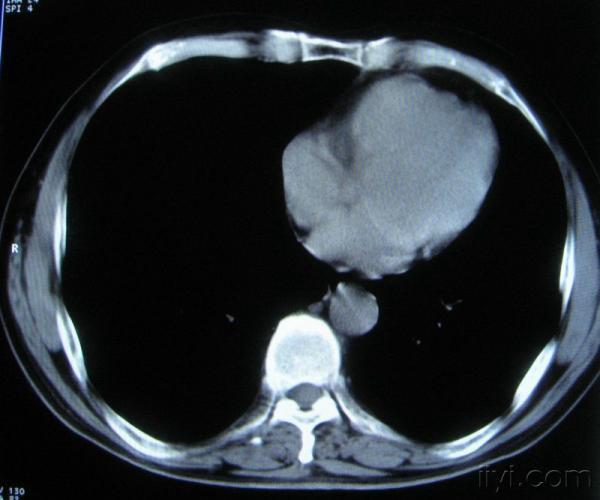

男。60岁,胸片示支气管炎治疗后复查CT。

你指那个肯定是淋巴结,中央系坏死,这很常见,特别在双侧腹股沟会经常看到。这个双侧腋窝及纵隔见多发小淋巴结征。

根据位置考虑应该是淋巴结,密度不均,是因为肿大的淋巴结中心液化坏死